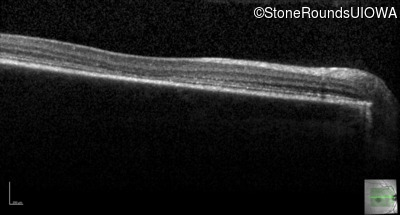

Optical Coherence Tomography - Right - 20/100 -1

Exemplar / OCT Stack